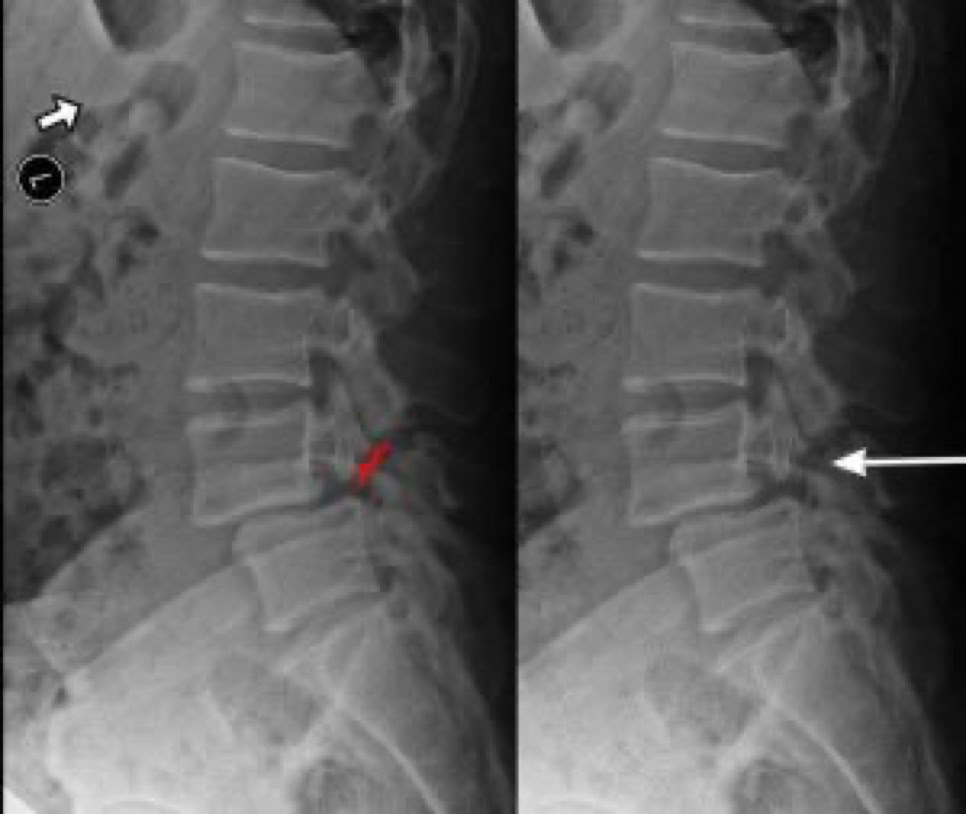

Spondylolisthesis is most commonly found in the lumbar spine as these levels bear the most weight. To assess instability, we take x-rays of a patient bending forward (flexion) and bending backwards (extension). Normally there would be no motion. The more motion seen between flexion and extension x-rays across an injured level, the greater the patient’s symptoms usually appear.

X-RAY SHOWING A PARS FRACTURE DEFECT

THE WHITE OUTLINE SHOWS THE SLIPPAGE.